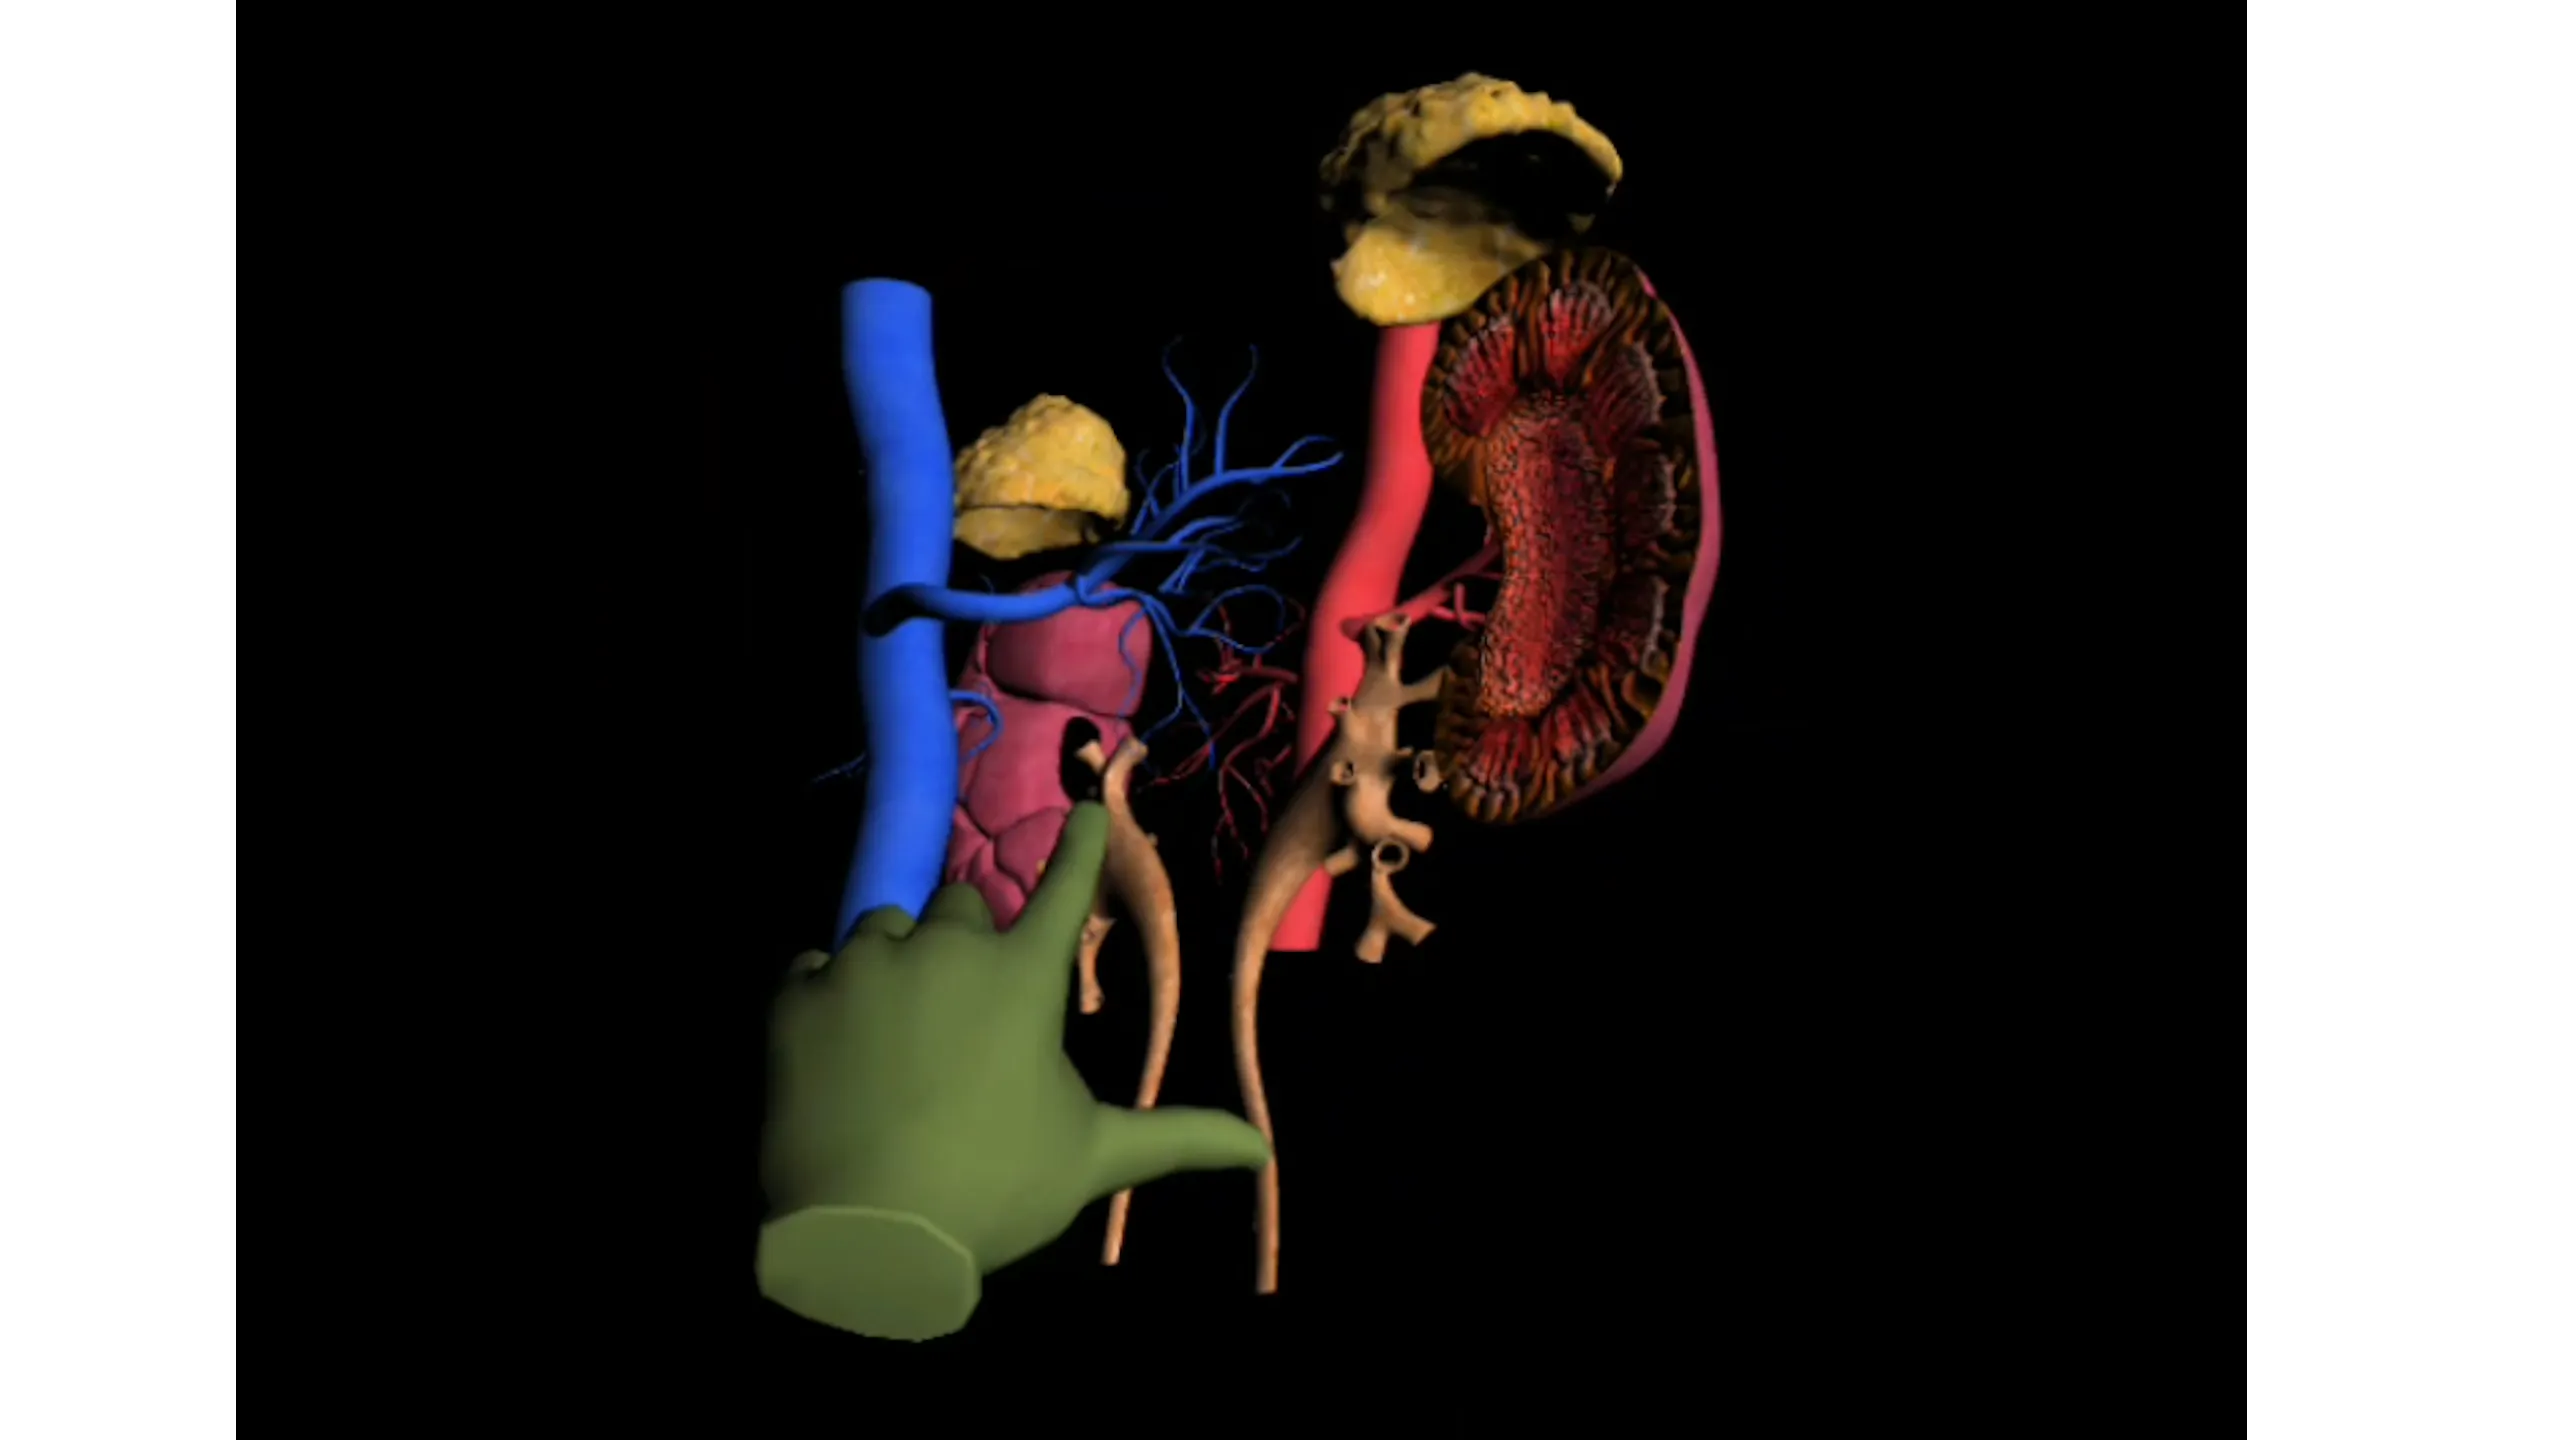

entrenar.se(学習)のスクリーンショット

スクリーンショット ※★画像をクリックすると拡大します。

新しいアプリでバーチャルリアリティがあなたの指の先にあります。

あなたのトレーニングは、私たちのバーチャルリアリティテクノロジーから恩恵を受けることができます。

バーチャルテクノロジーの学習で: